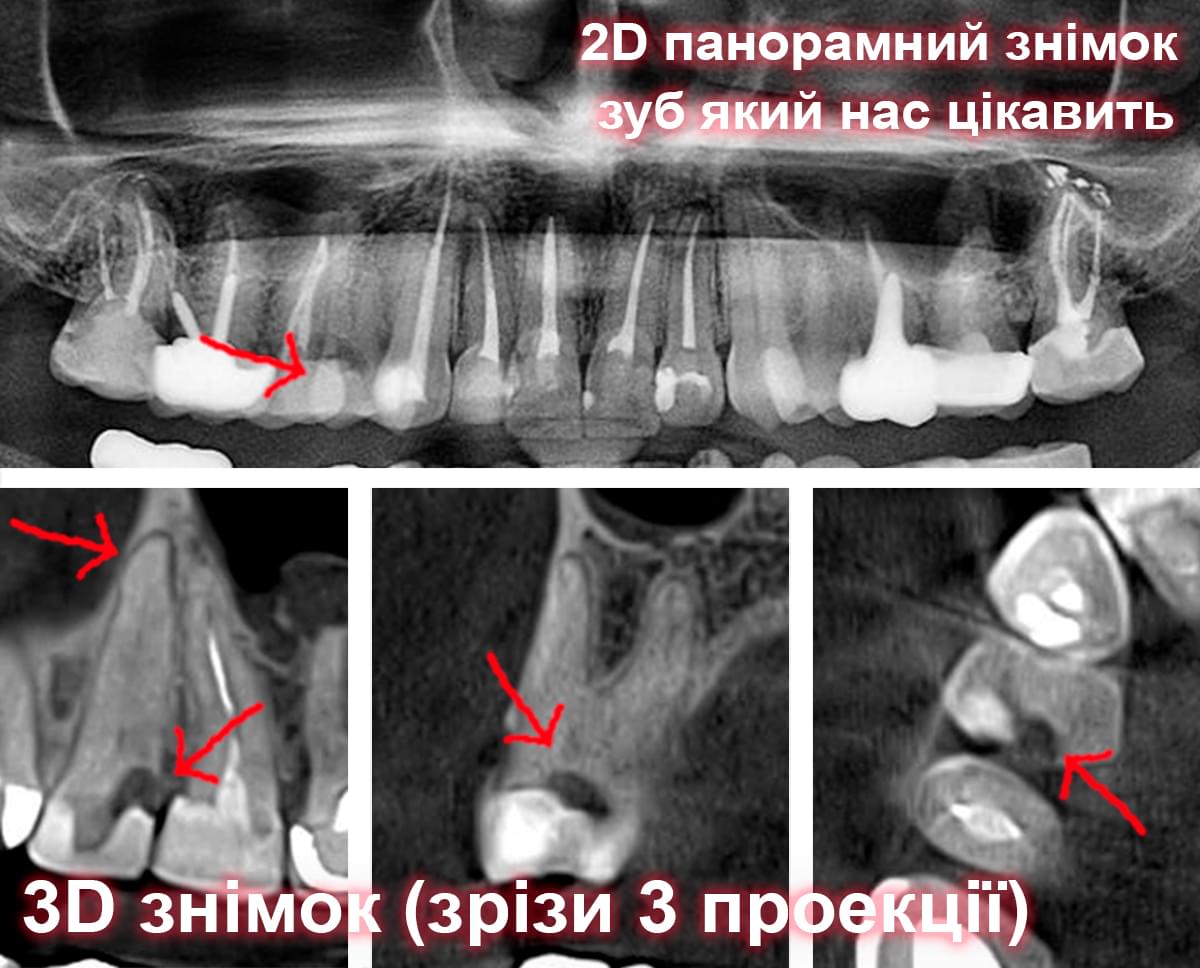

Візуальне порівняння (Кейс одного пацієнта)

Зуб — це не просто монолітний об'єкт, а складна система мікроканалів. На плоскому 2D-знімку вони часто перекривають один одного, створюючи ілюзію простої анатомії.

Непомічений канал — це джерело майбутньої інфекції та причина «загадкового» болю після лікування. Завдяки високій роздільній здатності обладнання MyRay, лікар бачить кожен мікронний канал ще до того, як візьме до рук інструмент.

Коли коріння «ховає сюрпризи» - Корені зубів часто мають складну кривизну, гачкоподібні закручення або розгалуження, які на звичайному 2D-знімку накладаються один на одного, створюючи ілюзію прямого каналу. На плоскій картинці неможливо побачити реальний об'єм та напрямок вигину, що критично важливо при видаленні «зубів мудрості» або ендодонтичному лікуванні. КТ MyRay дає змогу лікарю заздалегідь побачити 3D-геометрію кожного кореня, оцінити його близькість до нижньощелепного нерва чи гайморової пазухи та підібрати правильну тактику роботи. Це мінімізує ризики поломки інструменту в каналі або травмування сусідніх структур, перетворюючи складну хірургію на прогнозовану процедуру.